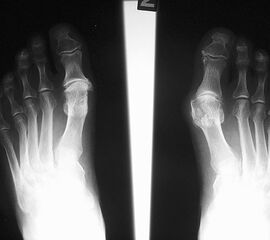

• Röntgenaufnahme des Vorfußes im Stand in 2 Ebenen (dorsoplantar, mediolateral)

• Beurteilung der degenerativen Veränderungen am Röntgenbild nach der Einteilung von Hattrup und Johnson (1988) 11.

• Beurteilung des Intermetatarsalwinkels (Intermetatarsal angle - IMA), des Hallux valgus Winkels (Hallux valgus angle - HVA) und des distalen Metatarsalegelenkflächenwinkels (Distal metatarsal articular angle - DMAA).